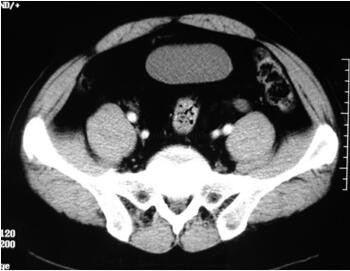

CT扫描:膀胱、直肠和乙状结肠被均一低密度(CT值为-40~-100HU)组织包裹和挤压,该组织无增强(图46-6~图46-8)。

图46-6 CT扫描:膀胱及结肠被低密度组织(CT值-40~-100HU)所包裹和挤压

图46-7 CT扫描:患者腹部膨隆(肥胖),膀胱位置抬高,双侧输尿管扩张、积水明显